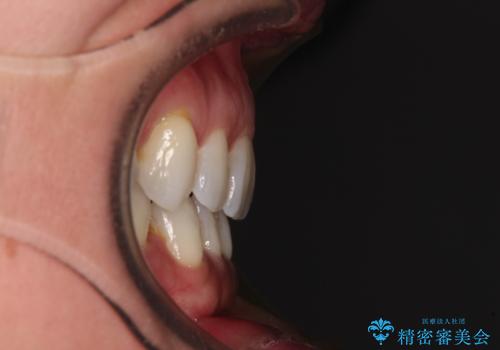

抜歯矯正の後戻りをインビザライン・ライトで解消

- 下顎前歯を中心に、以前行った矯正治療の後戻りが気になるとのことで来院された患者様です。

後戻りは軽度であったため、インビザライン・ライトにて治療を行うこととしました。

矯正治療後は、再度後戻りすることを極力回避するために、下顎前歯の舌側を細いワイヤーを用いて保定することとしました。